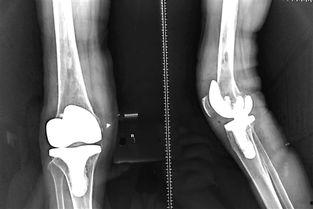

在手术之前,医生会对患者进行详细的检查,包括X光、CT等,以了解患者的膝关节状况。此外,医生还会对患者进行术前谈话,告知手术的风险和注意事项。

手术过程中,医生会首先将患者的膝关节取出,然后植入一个新的膝关节假体。这个假体通常由金属和塑料制成,具有很高的耐磨性和生物相容性。